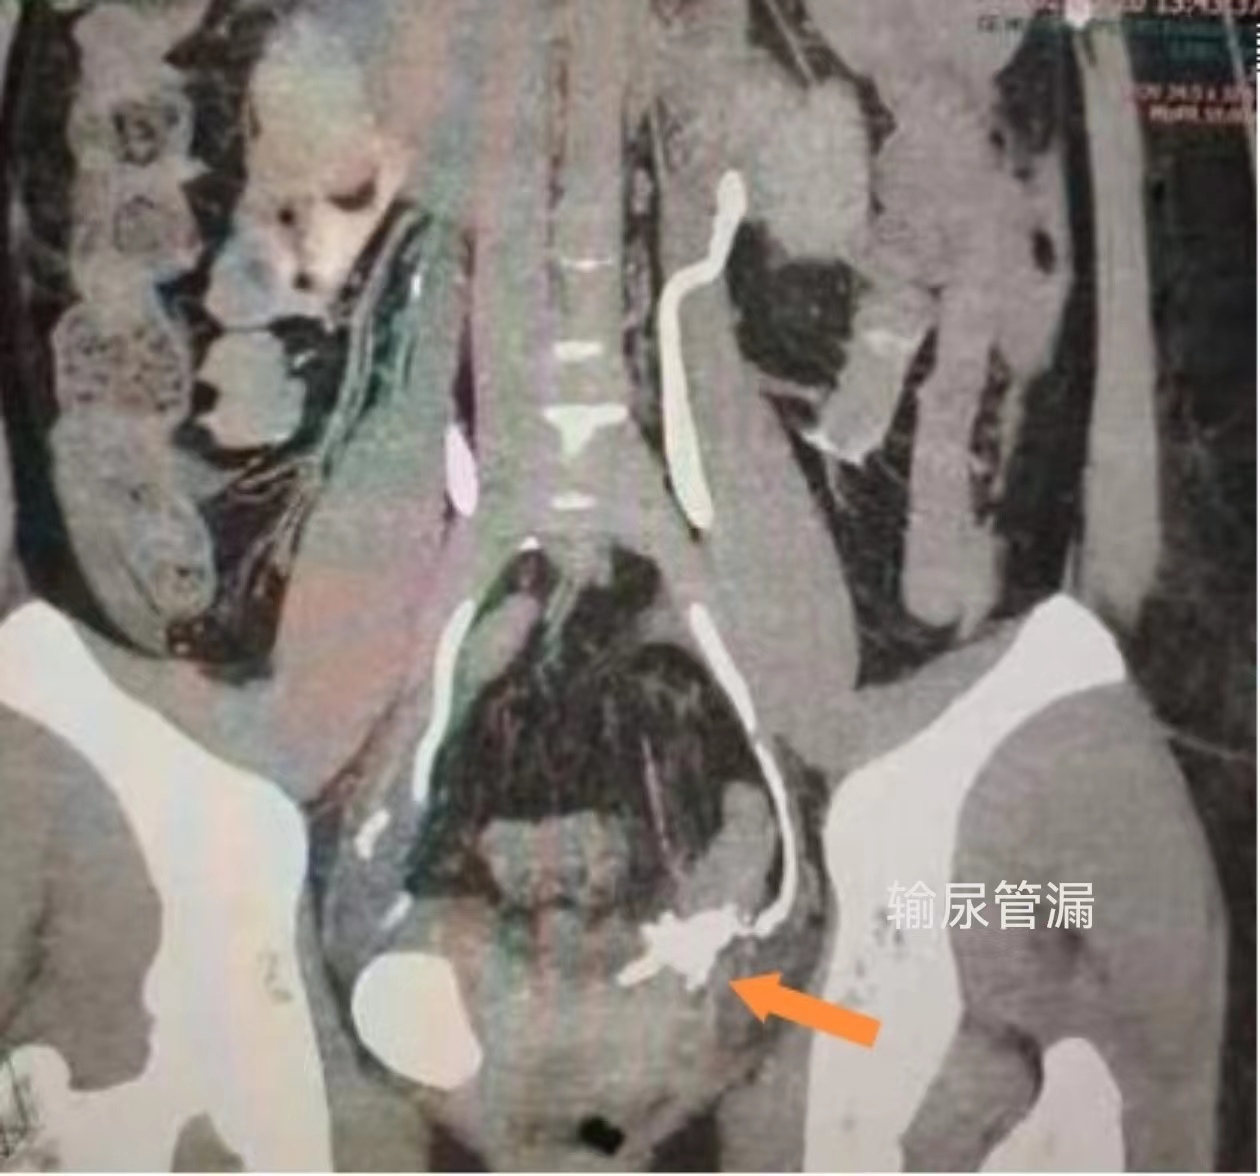

患者张女士今年34岁,因罹患妇科肿瘤,早些时候在外院接受了肿瘤切除手术。但是术后张女士出现尿漏,继发出现腹痛症状,并在术后两天转入医院泌尿外科进行治疗。经过泌尿外科团队细致检查,发现患者输尿管出现破溃,形成输尿管漏,尿液经过输尿管破口漏进入腹腔,引起感染。为尽快解决患者输尿管问题,医院泌尿外科首先进行急诊输尿管置管,但因患者输尿管损伤严重,DJ管置入失败。泌尿外科首席专家谷现恩和科主任龙建华带领泌尿外科医疗团队,认真分析患者病情后,决定创新采用输尿管镜和腹腔镜,双镜联合进行输尿管膀胱再植术。“通常进行输尿管膀胱再植术,一般都会采用膀胱高位再植,这样对于医生来说能够确保再植成功率。”龙建华介绍到,“但是这样会改变患者膀胱和输尿管的生理位置,如果患者以后上尿路再出现病变,则难以通过自然通道处理。这给患者以后的生活和治疗造成了不可逆的困难。所以为患者今后着想,我们和患者及家属沟通后,决定进行双镜联合输尿管膀胱再植术,最大程度为患者减少手术创伤。采用双镜联合的优势在于术中可以对吻合位置进行精准定位,术后输尿管与膀胱的解剖更加接近自然通路。”

龙建华作为本次手术的主刀医生,在泌尿外科团队和麻醉科、第一手术区的通力配合下,于6月22日进行了手术。手术中,龙建华凭借输尿管镜,精准定位了吻合口,并利用结合输尿管镜和腹腔镜的优势,精确进行了输尿管膀胱再植术。整个手术仅历时2小时,且取得了圆满成功。术后患者恢复情况良好,未出现任何并发症,并于7月2日顺利出院。